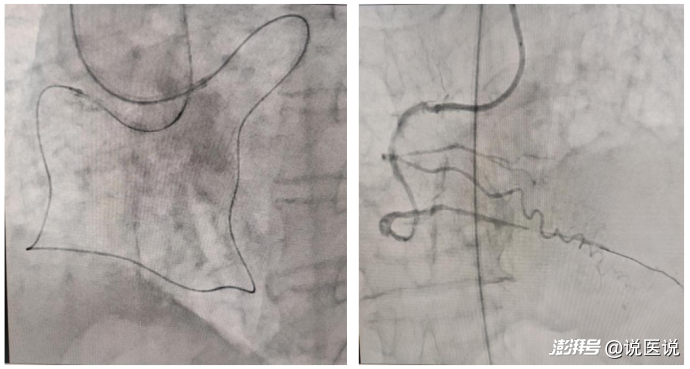

面對(duì)這一困境,馮建欽主任沒(méi)有絲毫猶豫,果斷決定采用逆向開(kāi)通技術(shù)——通過(guò)側(cè)支循環(huán)通道,在微導(dǎo)管支撐下,操控導(dǎo)絲在狹窄且曲折的血管中緩緩?fù)七M(jìn),使其和正向?qū)Ыz成功“會(huì)師”,患者右冠狀動(dòng)脈的閉塞段終于貫通。開(kāi)通閉塞段后,才發(fā)現(xiàn)右冠閉塞段長(zhǎng)達(dá)60mm,且嚴(yán)重迂曲。之后順利完成支架置入與藥物球囊擴(kuò)張,整個(gè)過(guò)程一氣呵成,手術(shù)圓滿成功。

手術(shù)中影像與開(kāi)通血管后影像

術(shù)后,齊大爺閉塞冠脈血管恢復(fù)TIMI3級(jí)血流,原本因缺血而憋悶的癥狀顯著改善,精神狀態(tài)也明顯好轉(zhuǎn)。